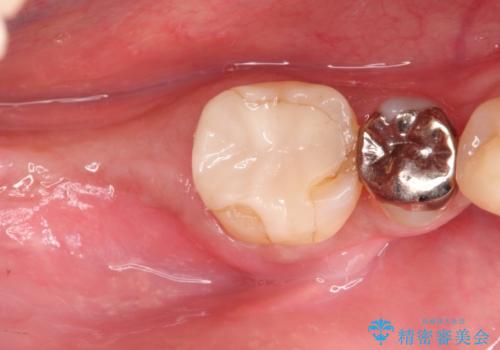

重度の歯周病により保存困難と診断し、抜歯後にインプラント治療を行いました。

抜歯後十分な骨の回復が認められず、単独の骨増生を行った後にインプラントを埋入しました。

インプラント埋入時に骨が足りない場合にはインプラント埋入前に骨増生を行います。また、インプラント周囲の角化歯肉が不足した場合は角化歯肉の移植も行うことがあります。

どちらの治療もインプラントの長期予後を高めるために必要な治療です。